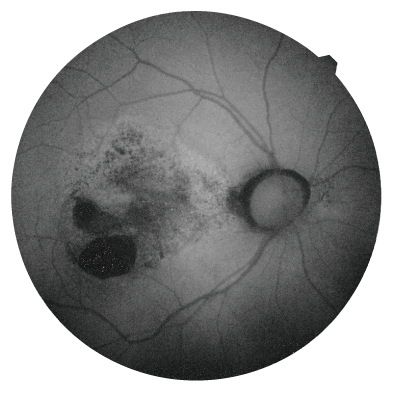

微細な変化も見つけやすい「Bスキャンデノイジングソフトウェア」(オプション)

多彩な機能でOCT撮影をサポート